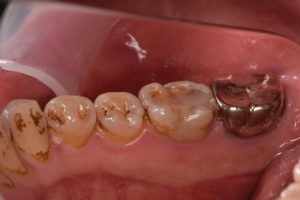

歯冠修復後

ジルコニアセラミッククラウン 132,000円(支台築造、仮歯代含む)

また根管治療後に適合の良い、再感染の起こりにくいジルコニアセラミッククラウンでしっかり再感染を防ぐことが根管治療の予後を左右します。

根管治療とともに歯冠修復物の精度がその歯の予後にとって極めて重要であると言えます。